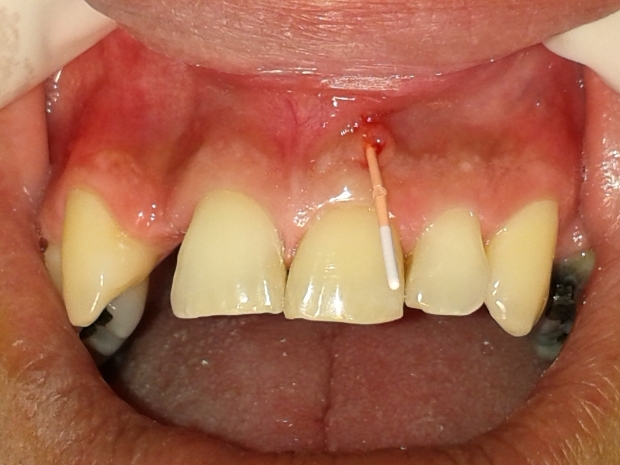

O mesmo relatava histórico de trauma dental na infância, sendo que previamente foi submetido a uma intervenção de urgência no elemento 21 por outro profissional, visto que se apresentava com edema e dor na região apical. Pela presença de fístula nesta região, foi realizado rastreamento na mesma, sendo a mesma oriunda do elemento dental 21 (figuras 2 e 3).

- Figura 2